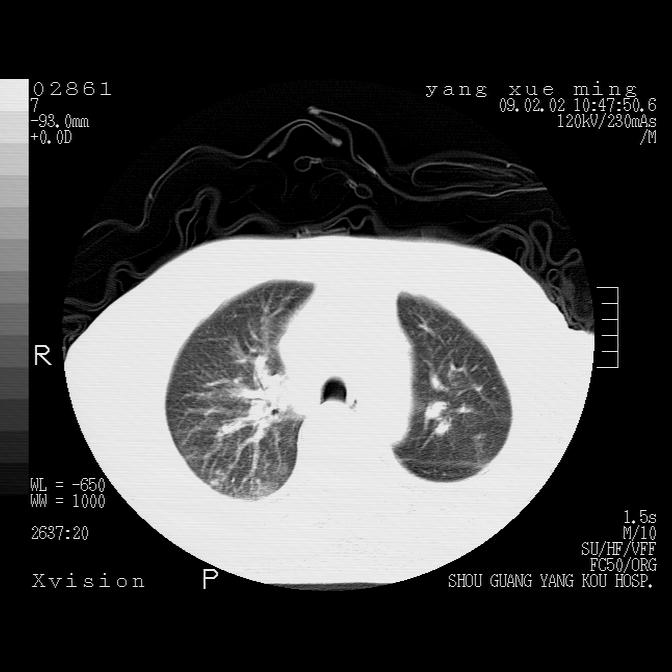

以下是引用zbp537在2009-2-3 19:08:00的发言:[br]我诊断为肺泡性肺水肿。[br]诊断依据:[br]1、心影普遍增大,肺血管增粗,并见絮状高密度影,肺门改变显著。[br]2、临床上表现胸闷咳嗽,无发烧,不是一个典型的肺部感染的病史。

以下是引用lkc8963在2009-2-3 20:11:00的发言:[br]1)右上肺陈旧病灶。2)右下肺团块及团片影,影像表现符合感染。3)左心增大,左冠脉钙化,符合冠心病。4)双侧肺门扩大,以左侧为著,肺动脉干略粗,左上肺局限性气肿,为谨慎起见,需除肿瘤,建议增强。

以下是引用lkc8963在2009-2-3 20:11:00的发言:[br]1)右上肺陈旧病灶.2)右下肺团块及团片影,影像表现符合感染.3)左心增大,左冠脉钙化,符合冠心病.4)双侧肺门扩大以左侧为著,肺动脉干略粗,左上肺局限性气肿,为谨慎起见,需除肿瘤,建议增强.